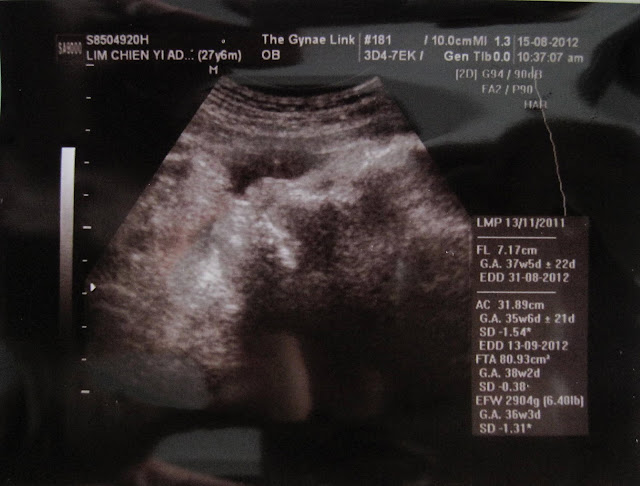

22nd August 2012 2:30am

41 weeks. My super bulging tummy.

In anther 8 hours time I'll be seeing Doctor Don again which I thought last week was my last appointment! Shall be doing another round of non-stress testing in the clinic. It's a belt strapped around my belly with a machine to listen to my girl movement and heart rate. Then the test will show whether she is healthy and moving enough. From there he would then advise if induction is needed. Though I very much want a natural birth (with epidural) but I guess God knows what's best for me and my girl. Shall keep my fingers crossed!

As placenta can get old it can stop my baby from growing or not getting enough oxygen or if it still does its job my girl may get too big and I may have hard time pushing her out and thus she may have to be born the caesarean section.